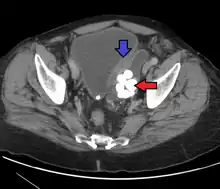

Diagnosis

Transitional refers to the histological subtype of the cancerous cells as seen under a microscope.